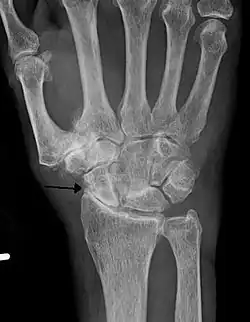

Diagnosis is made with reasonable certainty based on history and clinical examination.[52][53] X-rays may confirm the diagnosis. The typical changes seen on X-ray include: joint space narrowing, subchondral sclerosis (increased bone formation around the joint), subchondral cyst formation, and osteophytes.[54] Plain films may not correlate with the findings on physical examination or with the degree of pain.[55]

X-ray of erosive osteoarthritis of the fingers, also zooming in on two joints with the typical "gull-wing" appearance

Both primary generalized nodal osteoarthritis and erosive osteoarthritis (EOA, also called inflammatory osteoarthritis) are subsets of primary osteoarthritis. EOA is a much less common and more aggressive inflammatory form of osteoarthritis, which often affects the distal interphalangeal joints of the hand and has characteristic articular erosive changes on X-ray.[60]